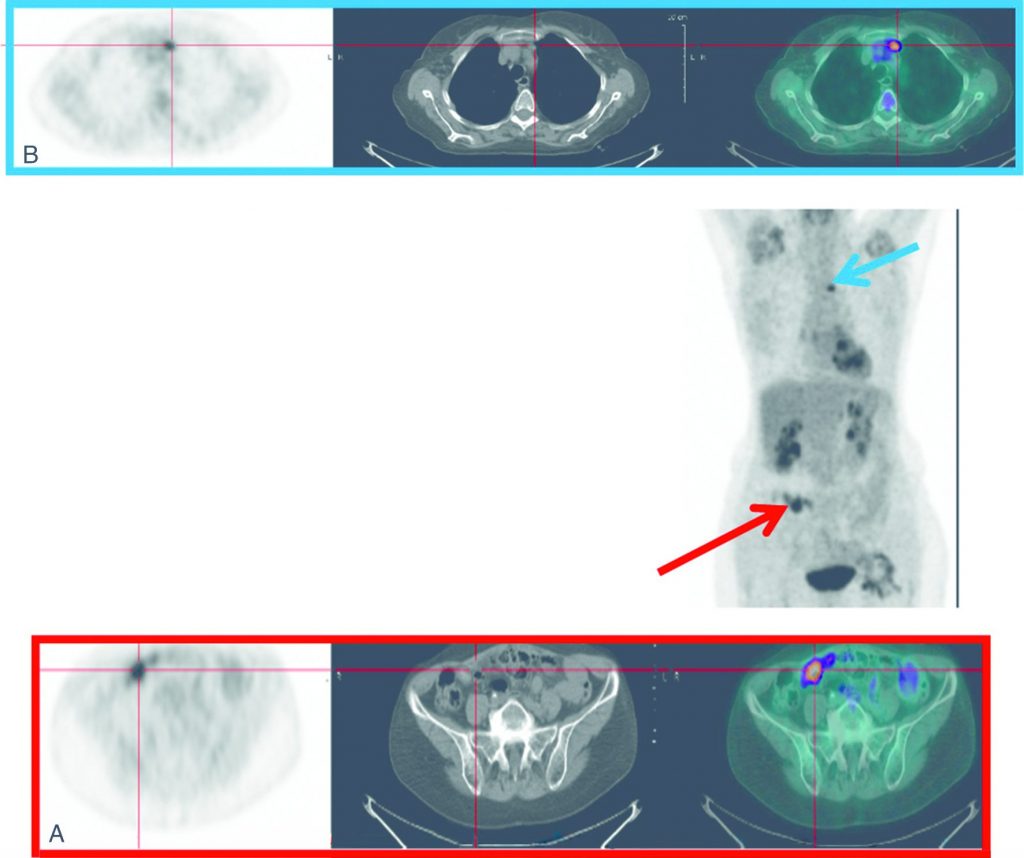

Fig. 23.2 Cancer de l’ovaire.

Lors du suivi, augmentation du CA125 à 56 UI/ml avec un bilan morphologique négatif. Découverte sur la TEP-TDM au 18FDG d’un nodule pelvien (flèche rouge) correspondant à une localisation péritonéale secondaire à l’analyse anatomopathologique.

Source : CERF, CNEBMN, 2022.

Fig. 23.3 TEP-TDM au 18FDG pour le bilan préchirurgical d’une suspicion de récidive d’un cancer de l’ovaire.

Visualisation de la récidive pelvienne correspondant à un nodule de carcinose péritonéale (A). Découverte d’une atteinte lymphatique médiastinale (B).